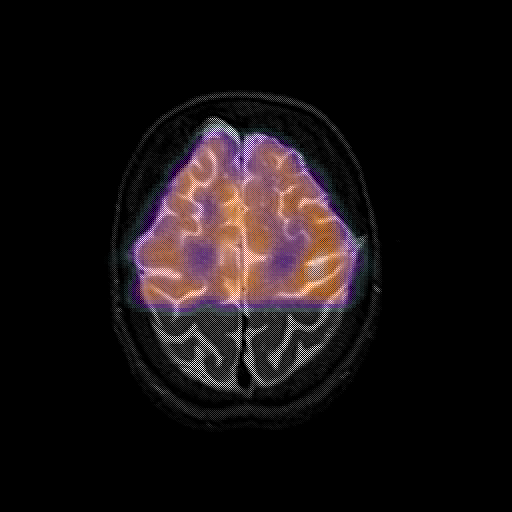

overlay 1: Slice 42

Slice 42

MRCBFCBF with

T1PDT2T1PDT2